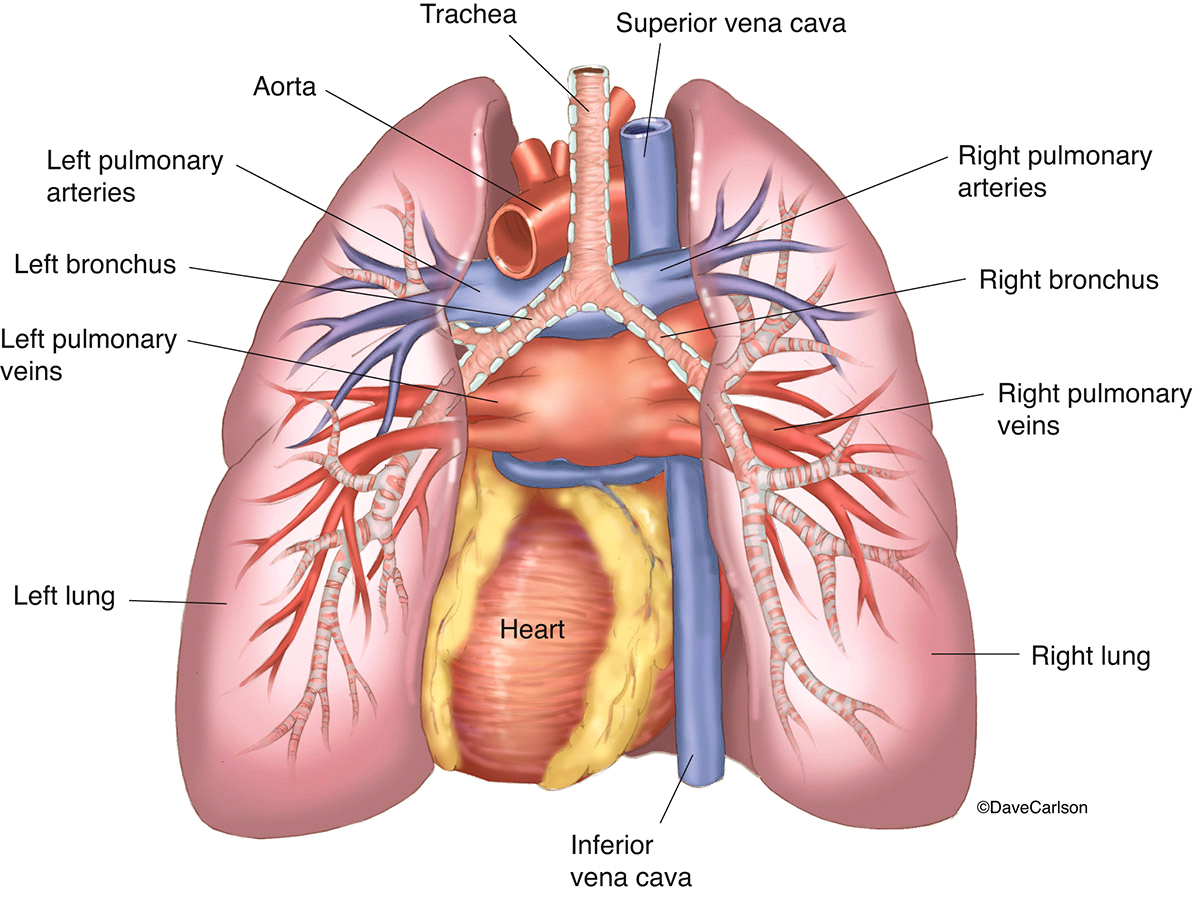

Lungs & Heart - Posterior View | Carlson Stock Art

lungs heart posterior vessels trachea bronchi pulmonary illustration